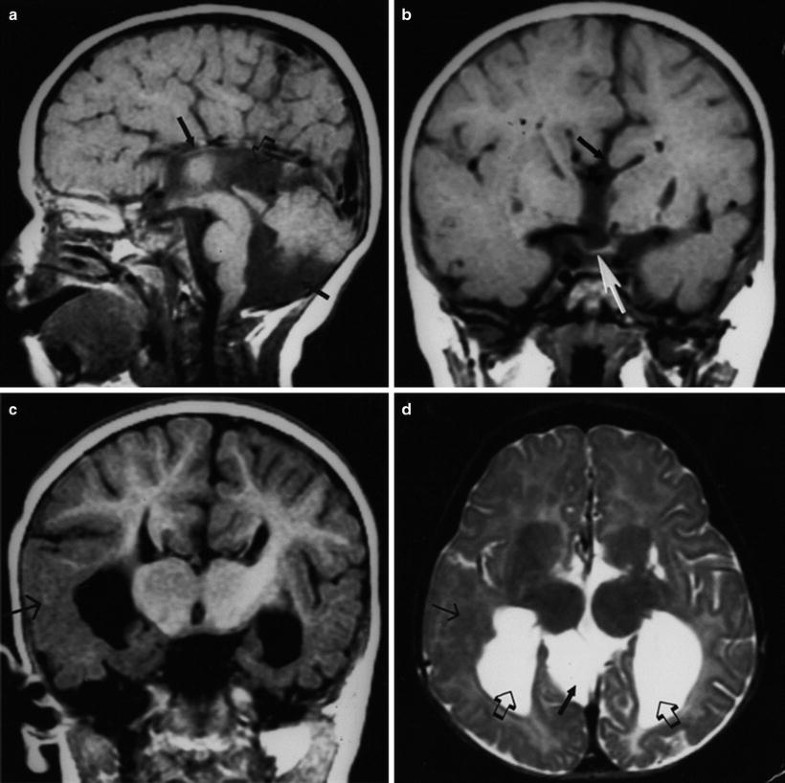

Cerebral Hemispheric Abnormalities

Cerebral hemispheric abnormalities associated with optic nerve hypoplasia. (a) Axial T1-weighted inversion recovery MR image demonstrating schizencephaly in patient with optic nerve hypoplasia. Schizencephalic cleft (arrows) consists of abnormal band of dysmorphic gray matter in left cerebral hemisphere extending from cortical surface to lateral ventricle. (b) T2-weighted axial MR image demonstrating asymmetrical periventricular leukomalacia, worse in right hemisphere (left side of picture), in child with optic nerve hypoplasia. Note enlargement and irregular contour of posterior aspect of lateral ventricle. Black arrow denotes loss of posterior periventricular white matter, with direct apposition of cortical gray matter to trigone of lateral ventricle. White arrow indicates greater volume of posterior periventricular white matter in the left hemisphere. With permission, from Brodsky and Glasier [58]. Copyright 1993, American Medical Association.